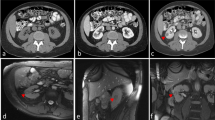

A 65-year-old female presenting with a 13-mm, radiologically indeterminate, endophytic left renal mass. a Axial unenhanced CT image demonstrates poor lesion conspicuity. Following contrast administration, the lesion was transiently visible on (b, arrow) arterial and (c, arrow) portal venous phase axial CT images. d B-Mode US image demonstrates multiple hyperechoic pseudo-nodules (arrows); the lesion seen on CT was not definitively identified. e Axial prone unenhanced T2-weighted MRI and (f) real-time MR fluoroscopy images clearly delineate the target-lesion (with overlaid planned needle trajectory in e). g–i Placement of biopsy system in the renal mass (arrows) under multi-planar MR-fluoroscopy guidance ((g) axial, (h) sagittal , and (i) coronal planes). The histopathological examination of the biopsy revealed a clear cell papillary renal cell carcinoma (ISUP grade 2) in hematoxylin and eosin (j), with characteristic immunohistochemical profile (negativity for α-methylacyl-CoA racemase/AMACR (k); diffuse reactivity for cytokeratin 7 (l); and membranous cup-like staining by carbonic anhydrase IX (m))